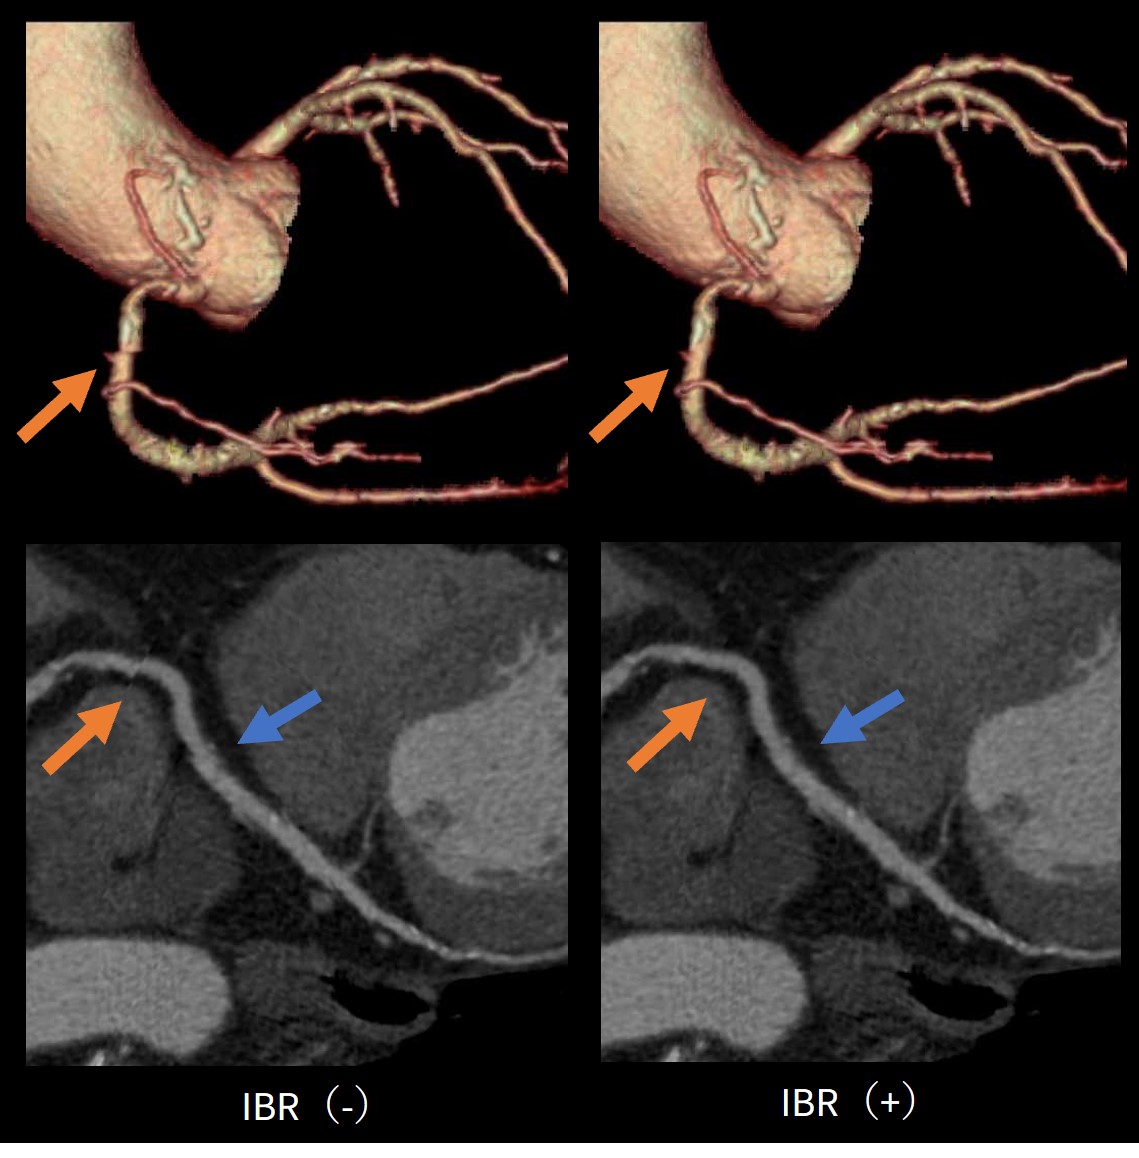

SSF2.0×IBRによるアーチファクト低減

SSF2.0を使用することでモーションアーチファクトを低減することはできるが、64列CTを使用している以上、バンディングアーチファクトの問題がある。

バンディングアーチファクトを低減させる機能としてIntelligent Boundary Registration(以下IBR)があり、本機能を用いることでデータ間の境界をぼかすことなく補正することができる。このIBRとSSF2.0を用いることでモーション及びバンディングアーチファクトが低減された冠動脈CT画像を提供することができる。

SSF20_ookawara08.jpg

Fig5.IBR症例